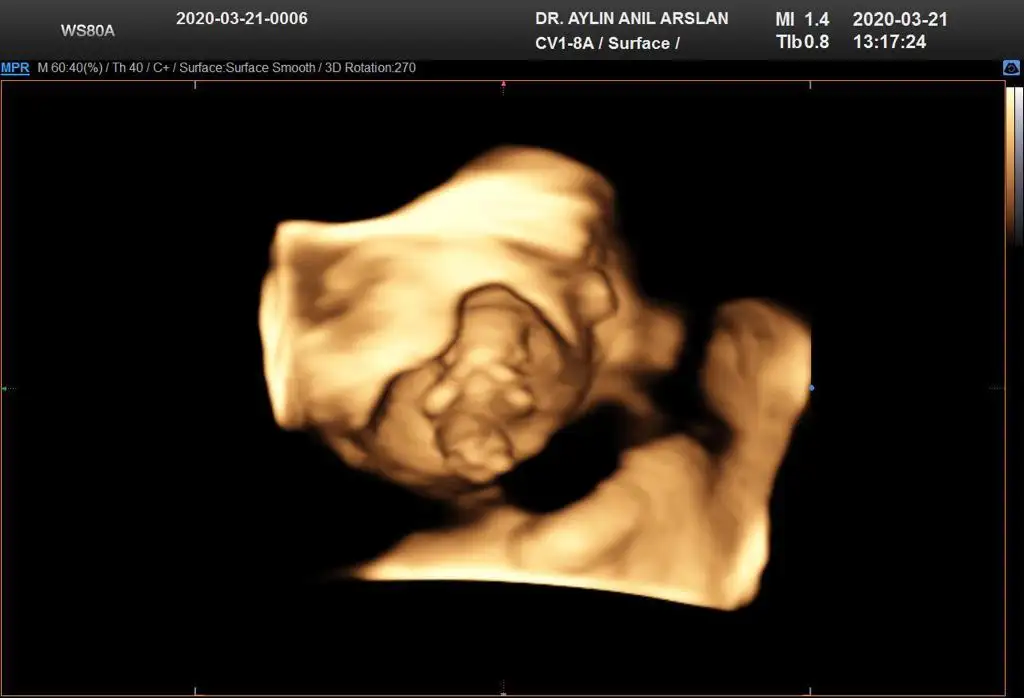

11+3 ama cok net değil gibi sanki yinede Bi tahmin isterim daha 5 hafta sonra öğrencez mecbur 😪

• IMG-20200321-WA0010.webp

IMG-20200321-WA0010.webp

25,9 KB · Görüntüleme: 44

• IMG-20200321-WA0011.webp

IMG-20200321-WA0011.webp

25,8 KB · Görüntüleme: 41

• IMG-20200321-WA0012.webp

IMG-20200321-WA0012.webp

25,8 KB · Görüntüleme: 40

• IMG-20200321-WA0009.webp

IMG-20200321-WA0009.webp

17,6 KB · Görüntüleme: 34

• IMG-20200321-WA0006.webp

IMG-20200321-WA0006.webp

17,6 KB · Görüntüleme: 37